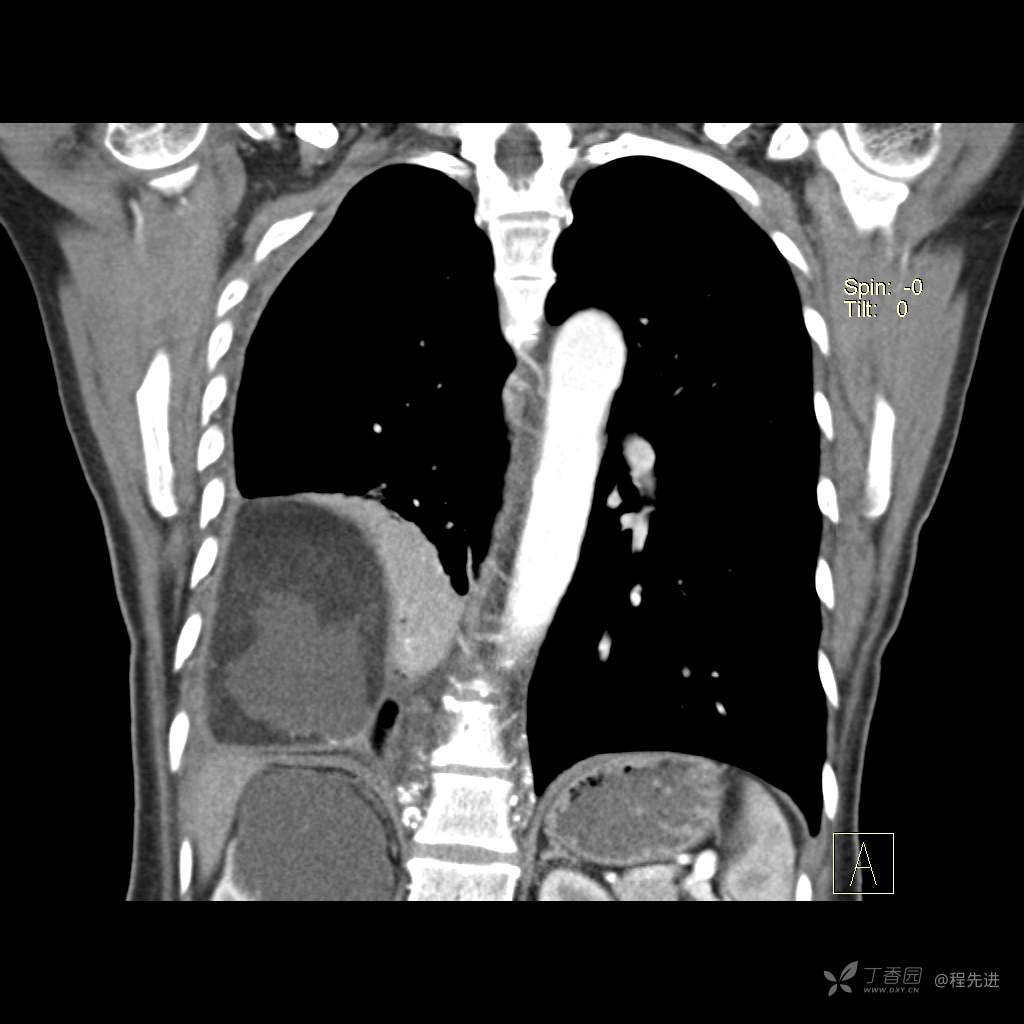

患者性别:女

患者年龄:51岁

简要病史:胸闷半年